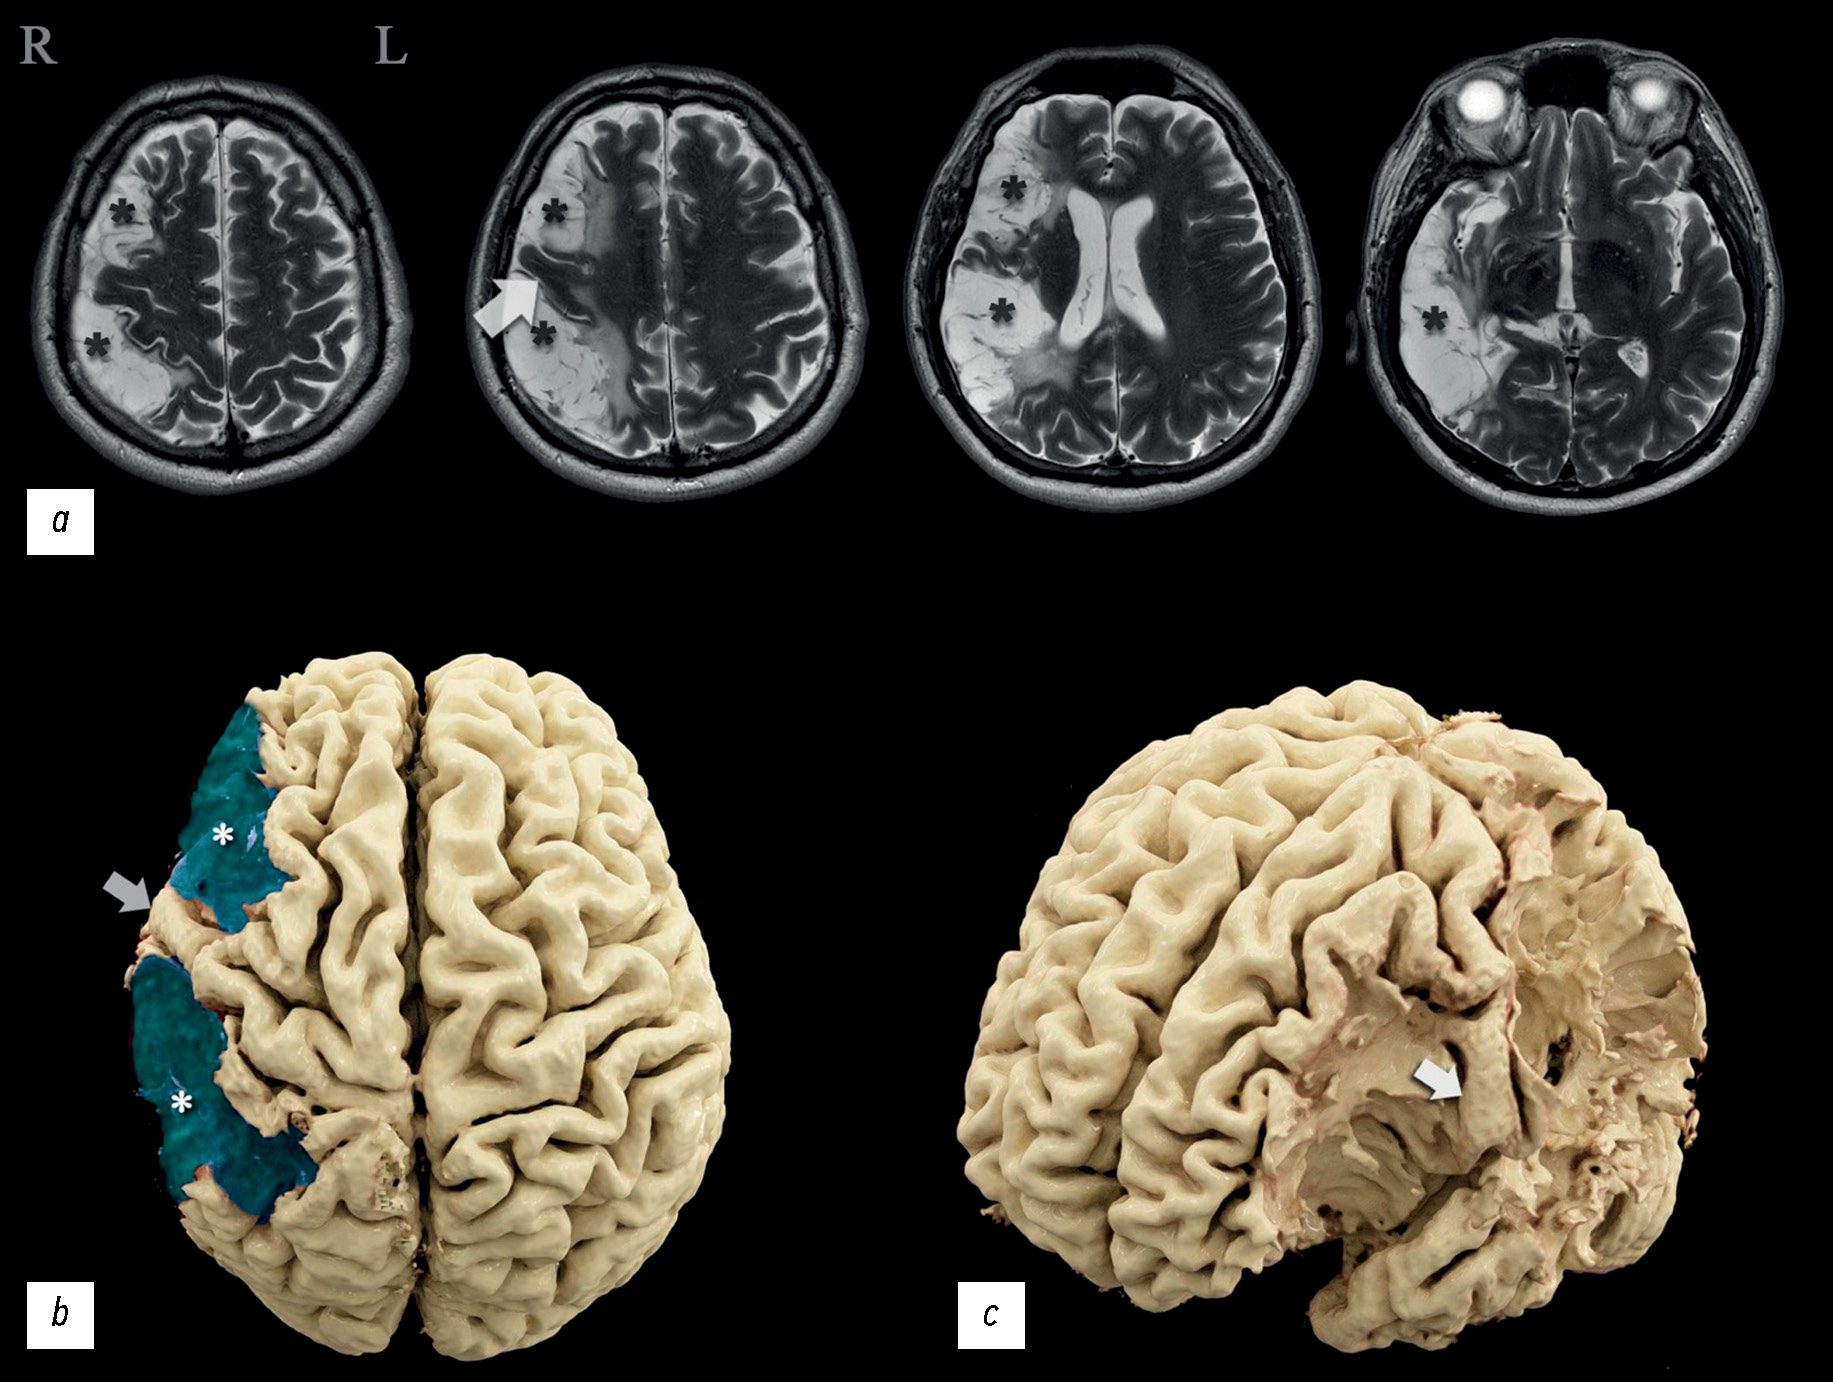

В рассматриваемом клиническом случае пациента, поступившего на реабилитацию после двух перенесенных ишемических инсультов, были проведены осмотры невролога и нейропсихолога, комплексное инструментальное исследование с применением электроэнцефалографии, магнитно-резонансной томографии, компьютерной томографии с оценкой перфузии, магнитно-резонансной трактографии , функциональной магнитно-резонансной томографии. У пациента наблюдался минимальный парез левых конечностей, нарушение произвольной регуляции деятельности, снижение нейродинамических показателей лёгкой степени выраженности, негрубого снижения внимания и критического отношения к своему состоянию. По результатам нейровизуализации были обнаружены признаки обширного постинфарктного повреждения правого субдоминантного полушария головного мозга в бассейне средней мозговой артерии.

Показано несоответствие объёма поражения мозга и тяжести клинических проявлений, проанализированы возможные причины имеющих место несоответствий. На основании данных функциональных исследований определено доминантное полушарие и предположен возможный вариант перестройки функциональных центров. Проведено сравнение с похожими клиническими случаями, проанализирована их связь с представленным в настоящей статье. Получены сведения, которые расширяют представления о топике изменённых зон, отвечающих за реализацию двигательной, речевой функций и способность к арифметическому счёту.